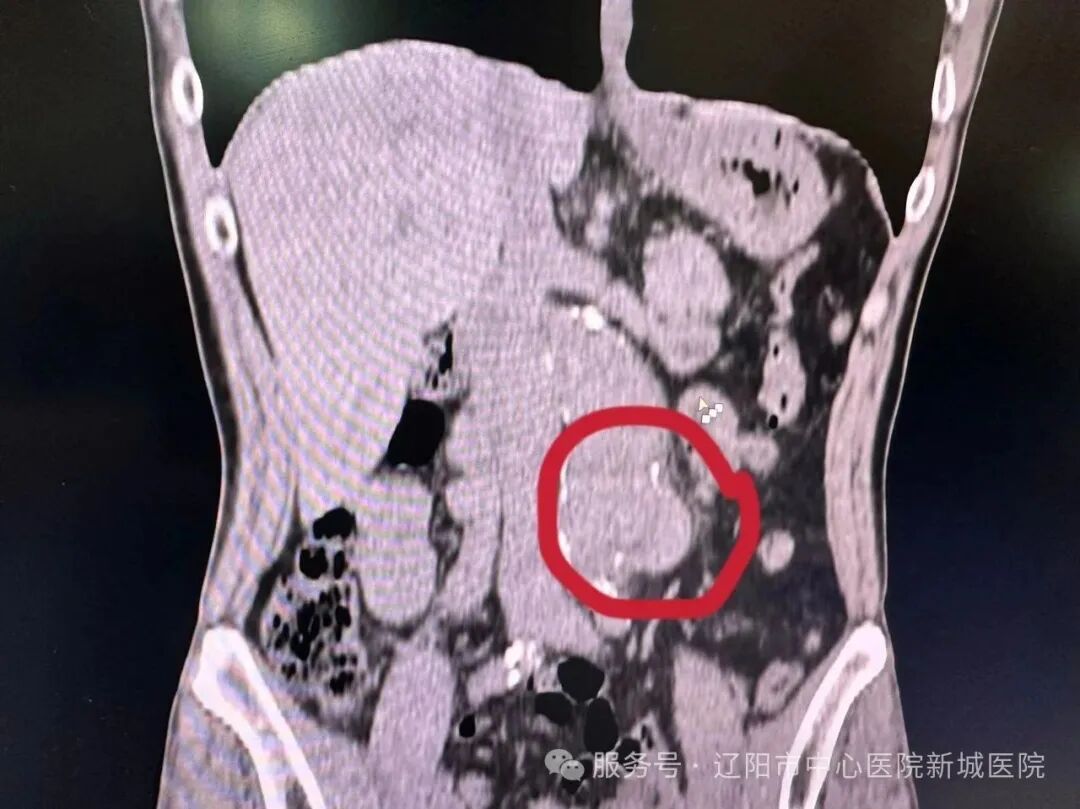

近日,一次常规门诊CT检查,在潘先生身上照出惊人一幕:腹主动脉瘤,腹主动脉壁上赫然膨出一个“定时炸弹”!这颗随时可能破裂的“炸弹”,让平静的门诊瞬间涌起紧张暗流。

腹主动脉瘤素来凶险,瘤体一旦破裂,九成患者抢救不及,生命将如风中残烛,片刻即灭。发现腹主动脉瘤必须立即转往具备血管外科手术能力的上级医院,生命通道刻不容缓。